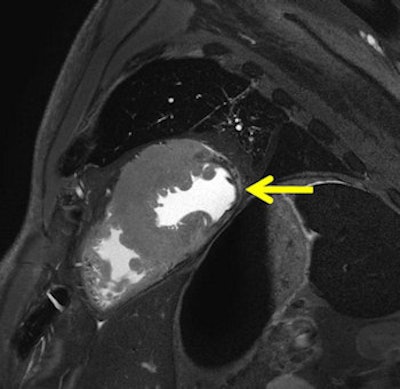

Acute myocardial infarction in postmortem MRI (death occurred after two to three days). A T2-weighted short axis image demonstrates a hypointensity with surrounding edema within the lateral wall. Autopsy revealed a yellowish alteration at the same location (not shown). Histology demonstrated early granulocyteous infiltration (not shown).